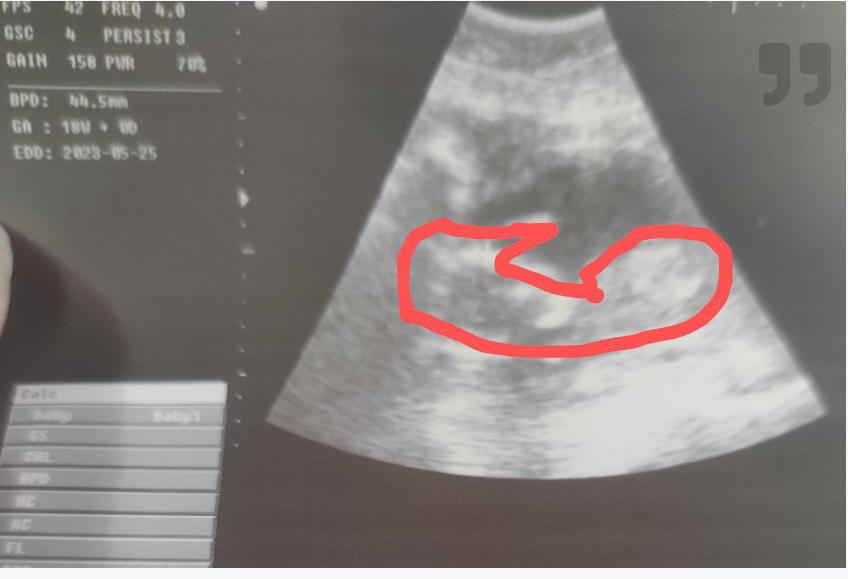

Момичета, какво виждате на тези снимки?

6+6 г.с и измерен пулс. Това жълтъчно мехурче или бебчето е? На моя приятелка са.